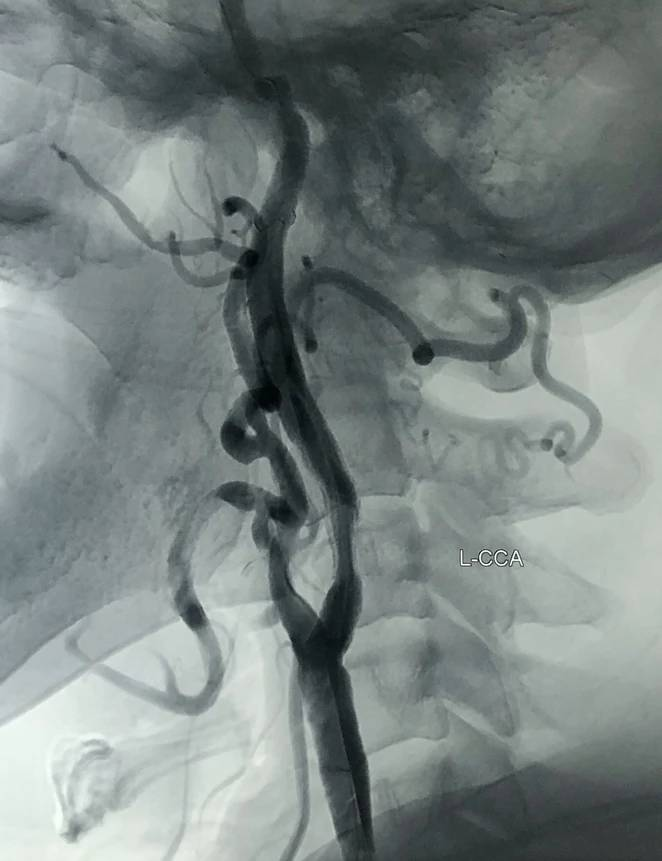

CTA确认:支架内重度再狭窄;

CTA确认:支架上端位于C2锥体上缘;颈内动脉内释放的6mm支架的直径“大于”远心端颈内动脉的直径。

血管造影显示:颈动脉极重度再狭窄,不能确认支架和远心端颈内动脉之间直径的差异。

超声显示:颈动脉重度狭窄,斑块内低回声(出血?),支架内不均质回声(血栓形成?)